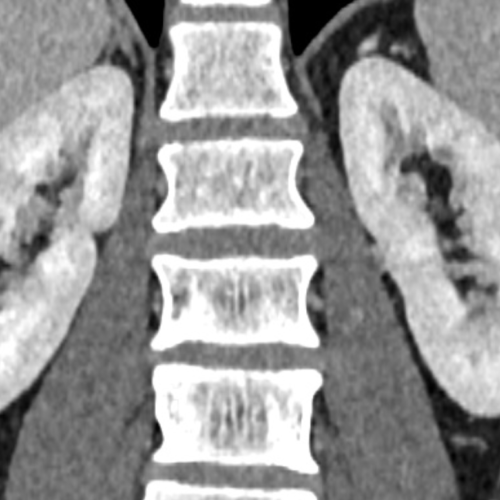

Cet examen est réalisé pour analyser le rein, les uretères et la vessie. Les autres structures anatomiques de l’abdomen seront également analysées.

Le scanner rénal est réalisé en cas de douleurs, de masse rénal, d’hématurie.

Quels sont les résultats possibles d’un scanner rénal (uroscanner) ?

Cette examen permets de diagnostiquer:

- Les lithiases (calculs rénaux) .

- Les tumeurs rénales .

- Les abcès .

- Les pyélonéphrites

- Les dilatations des cavités rénales

- Les sténoses des artères rénales